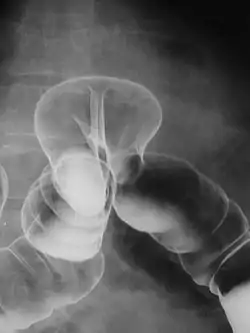

במהלך הבדיקה הרופא מחדיר לגוף תמיסה סמיכה ולבנה של מלחי בריום שמשמשת כחומר ניגוד, ועוקב אחר מעבר החומר בגוף באמצעות טכנולוגיה הקרויה פלואורוסקופיה שהיא מכונת שיקוף רנטגן המשתמשת בעיבוד דיגיטלי שמאפשר צפייה רצופה במסך טלוויזיה ואף יכולת הקלטת וידאו או תמונות סטילס. הבדיקה נעשית על ידי רופא רדיולוג, בסיוע של רנטגנאי.

מלחי הבריום מופיעים בתצלומים בצבע לבן ומדגימים את המבנה של מערכת העיכול, ואת קווי המתאר ואת הציפוי של דרכי העיכול. הבריום מצטבר באזורים בעייתים, ומסמן כיבים, חסימות וגידולים.

בדיקת ושט-קיבה-תריסריון - UGI

בדיקה זו מתחילה בעמידה. הנבדק מתבקש לבלוע את תמיסת הבריום, תוך כדי שיקוף, כדי לשלול בעיות בליעה. השיקוף נעשה מספר פעמים מזוויות שונות. לאחר מכן ניתנת לנבדק תמיסת גרגרים מוגזת כדי לנפח את הקיבה. מכיוון שהתמיסה בולטת בצילום ניתן לאבחן בעיות שונות כמו ליקויים אנטומיים, בעיות בהתכווצויות של הוושט ועוד. לאחר מכן המשך הבדיקה נעשה בשכיבה כדי לבדוק האם ישנו רפלוקס קיבתי ושטי, ובכדי לשלול בעיות שעלולות להיות קיימות בקיבה או בתריסריון. זמן הבדיקה הוא כחצי שעה.